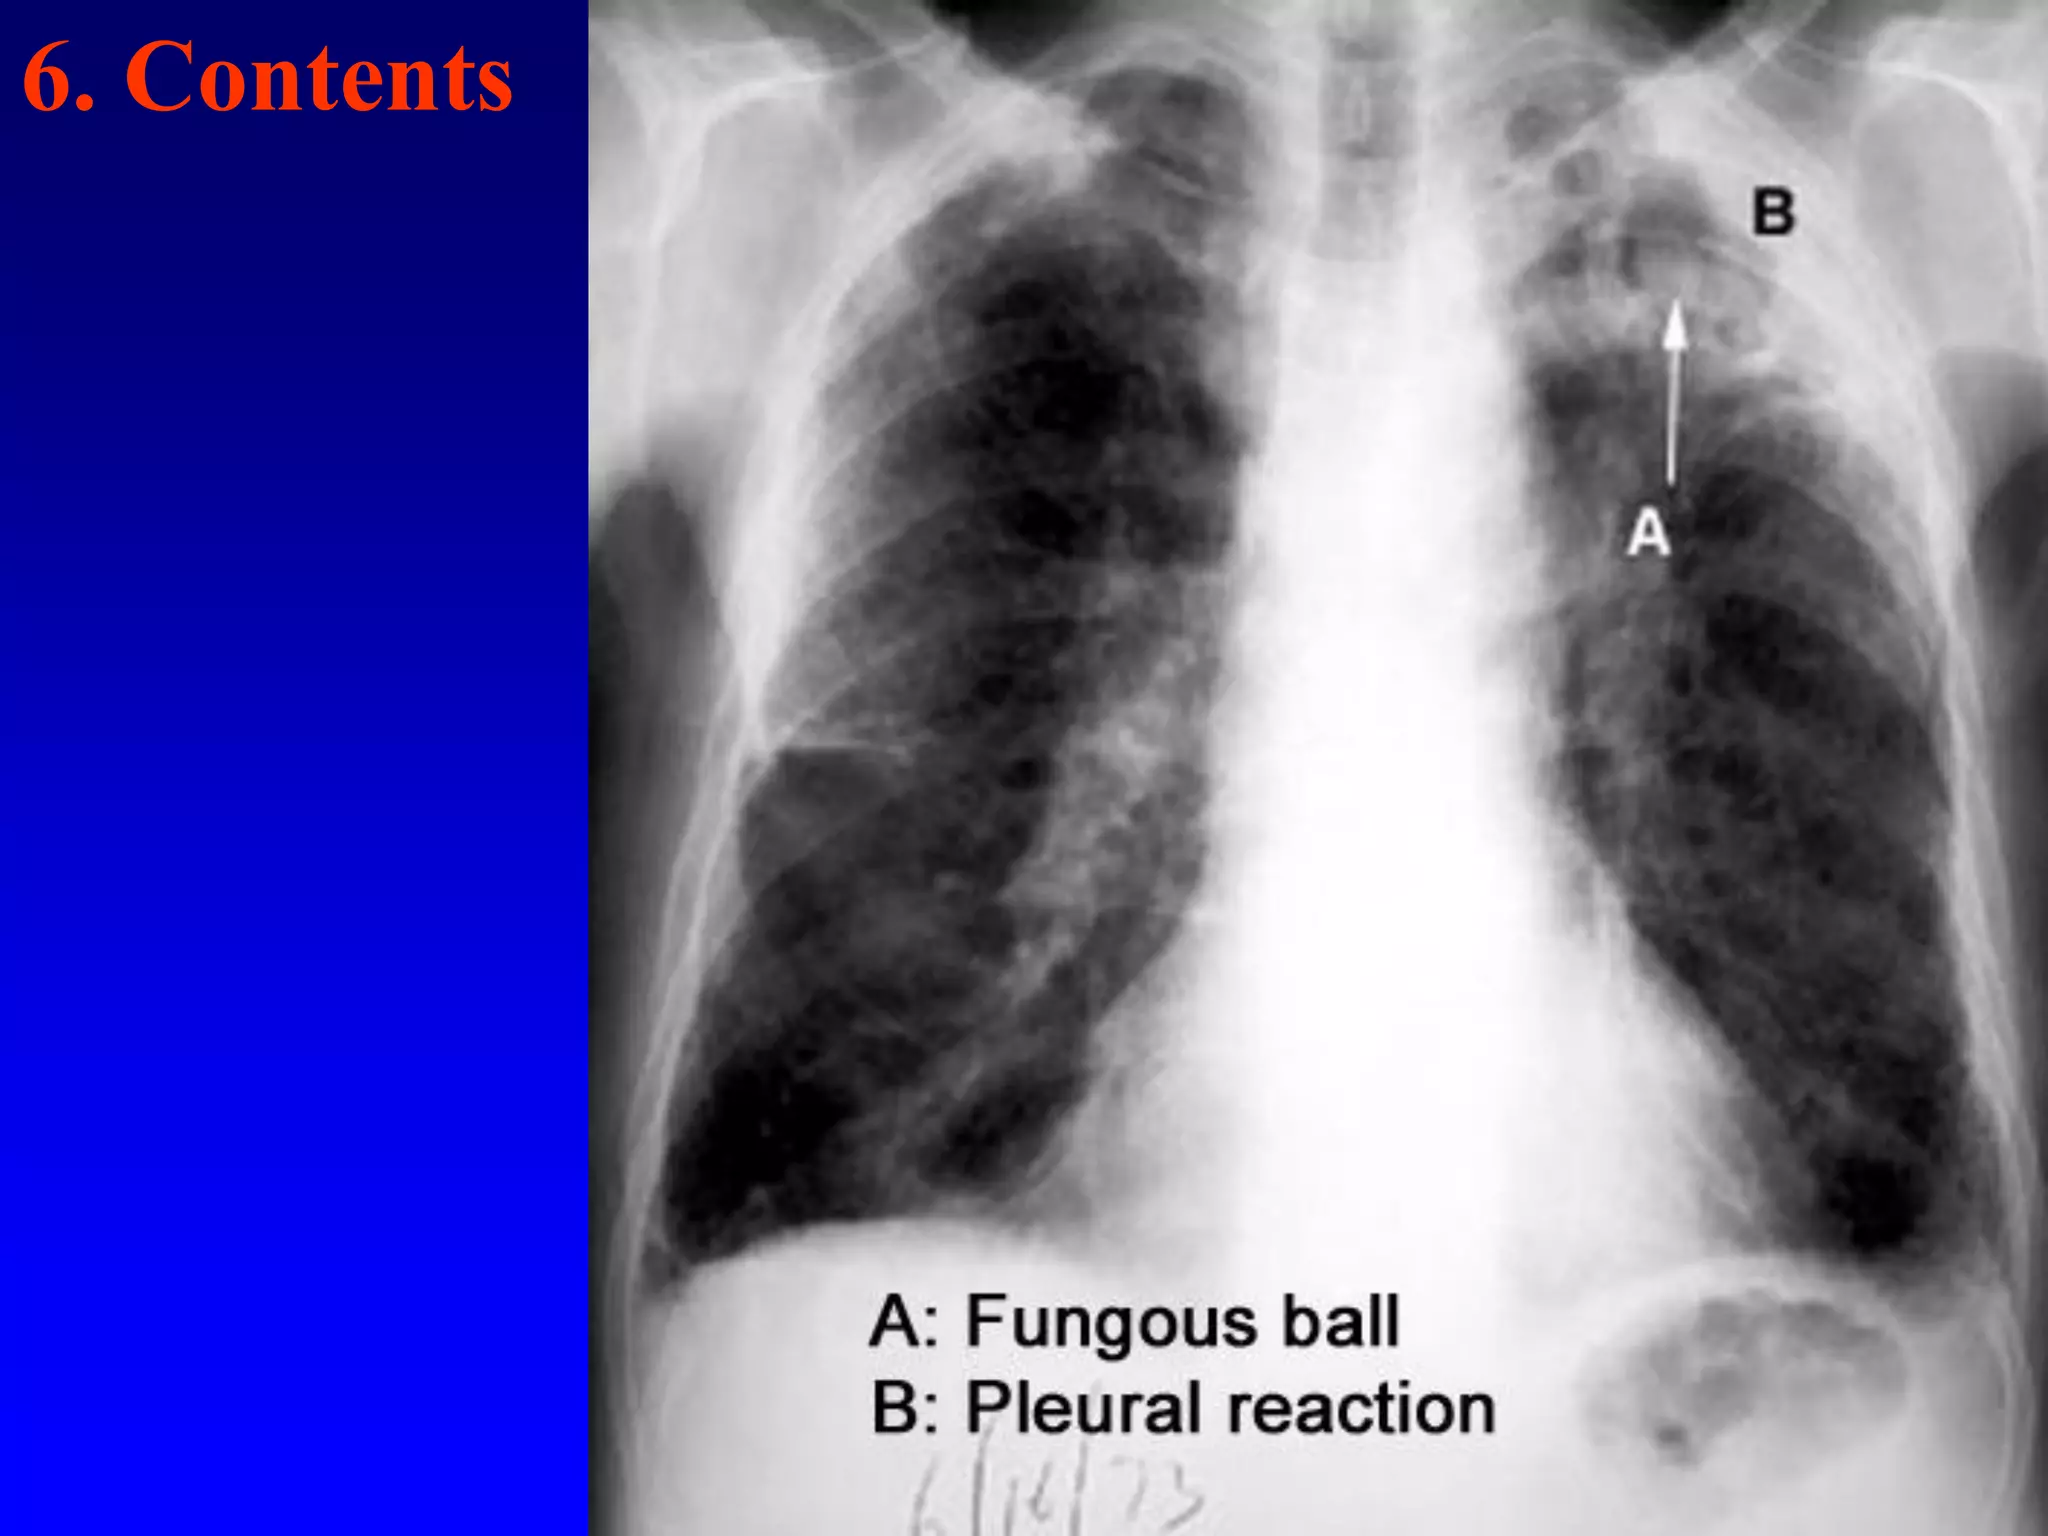

6. Contents

•Arrow head  Crescent sign.

Contents:

• A fungous ball should make you consider

aspergillosis. A blood clot and fibrin ball will